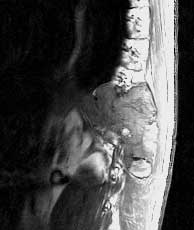

T1 sagittals pre-gad

Findings:

Extensive soft tissue mass in the left paraspinal and chest wall region with mixed signal.